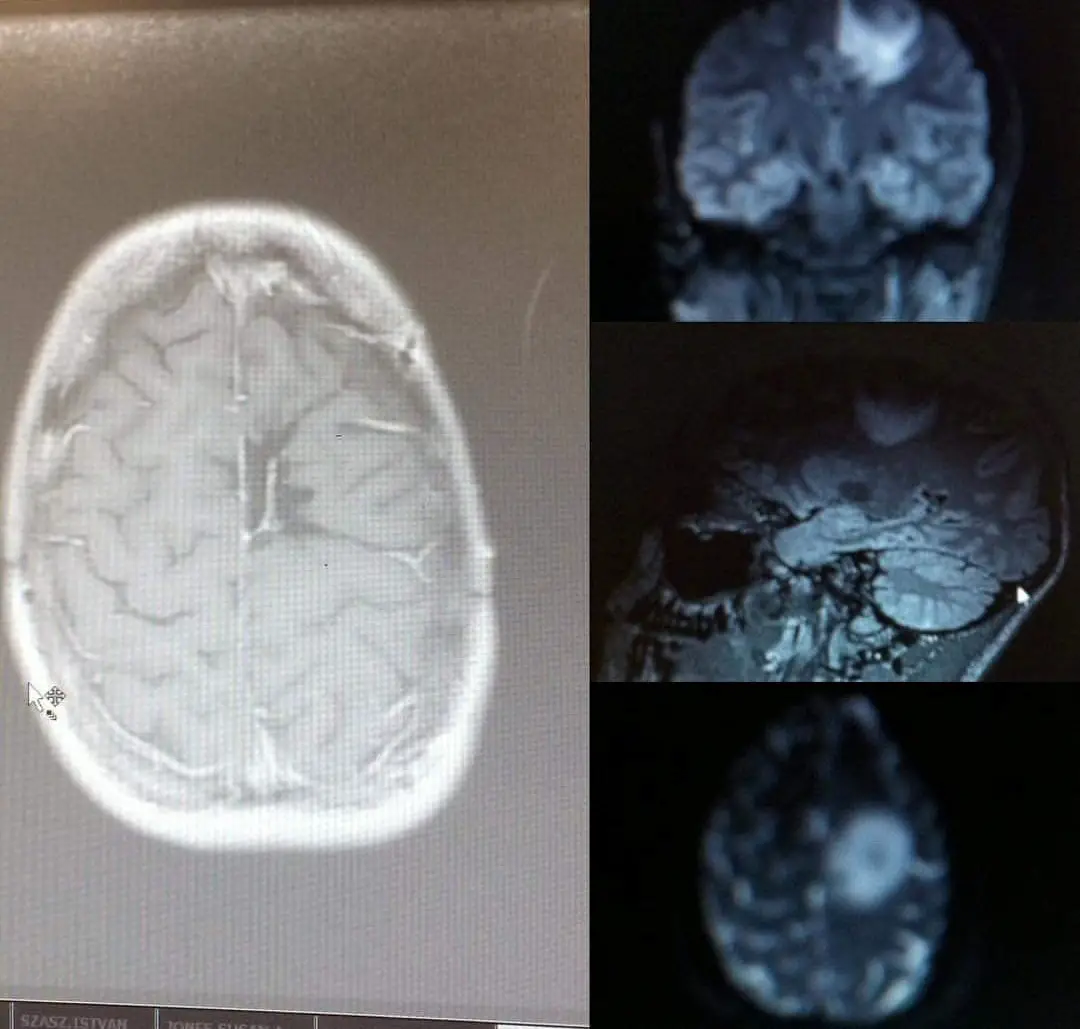

The 34-year-old was diagnosed with a grade four cancer after the discovery of an astrocytoma - a brain and spinal cord tumor that had grown as large as a golf ball - and went through surgery, chemotherapy and radiotherapy to remove it.